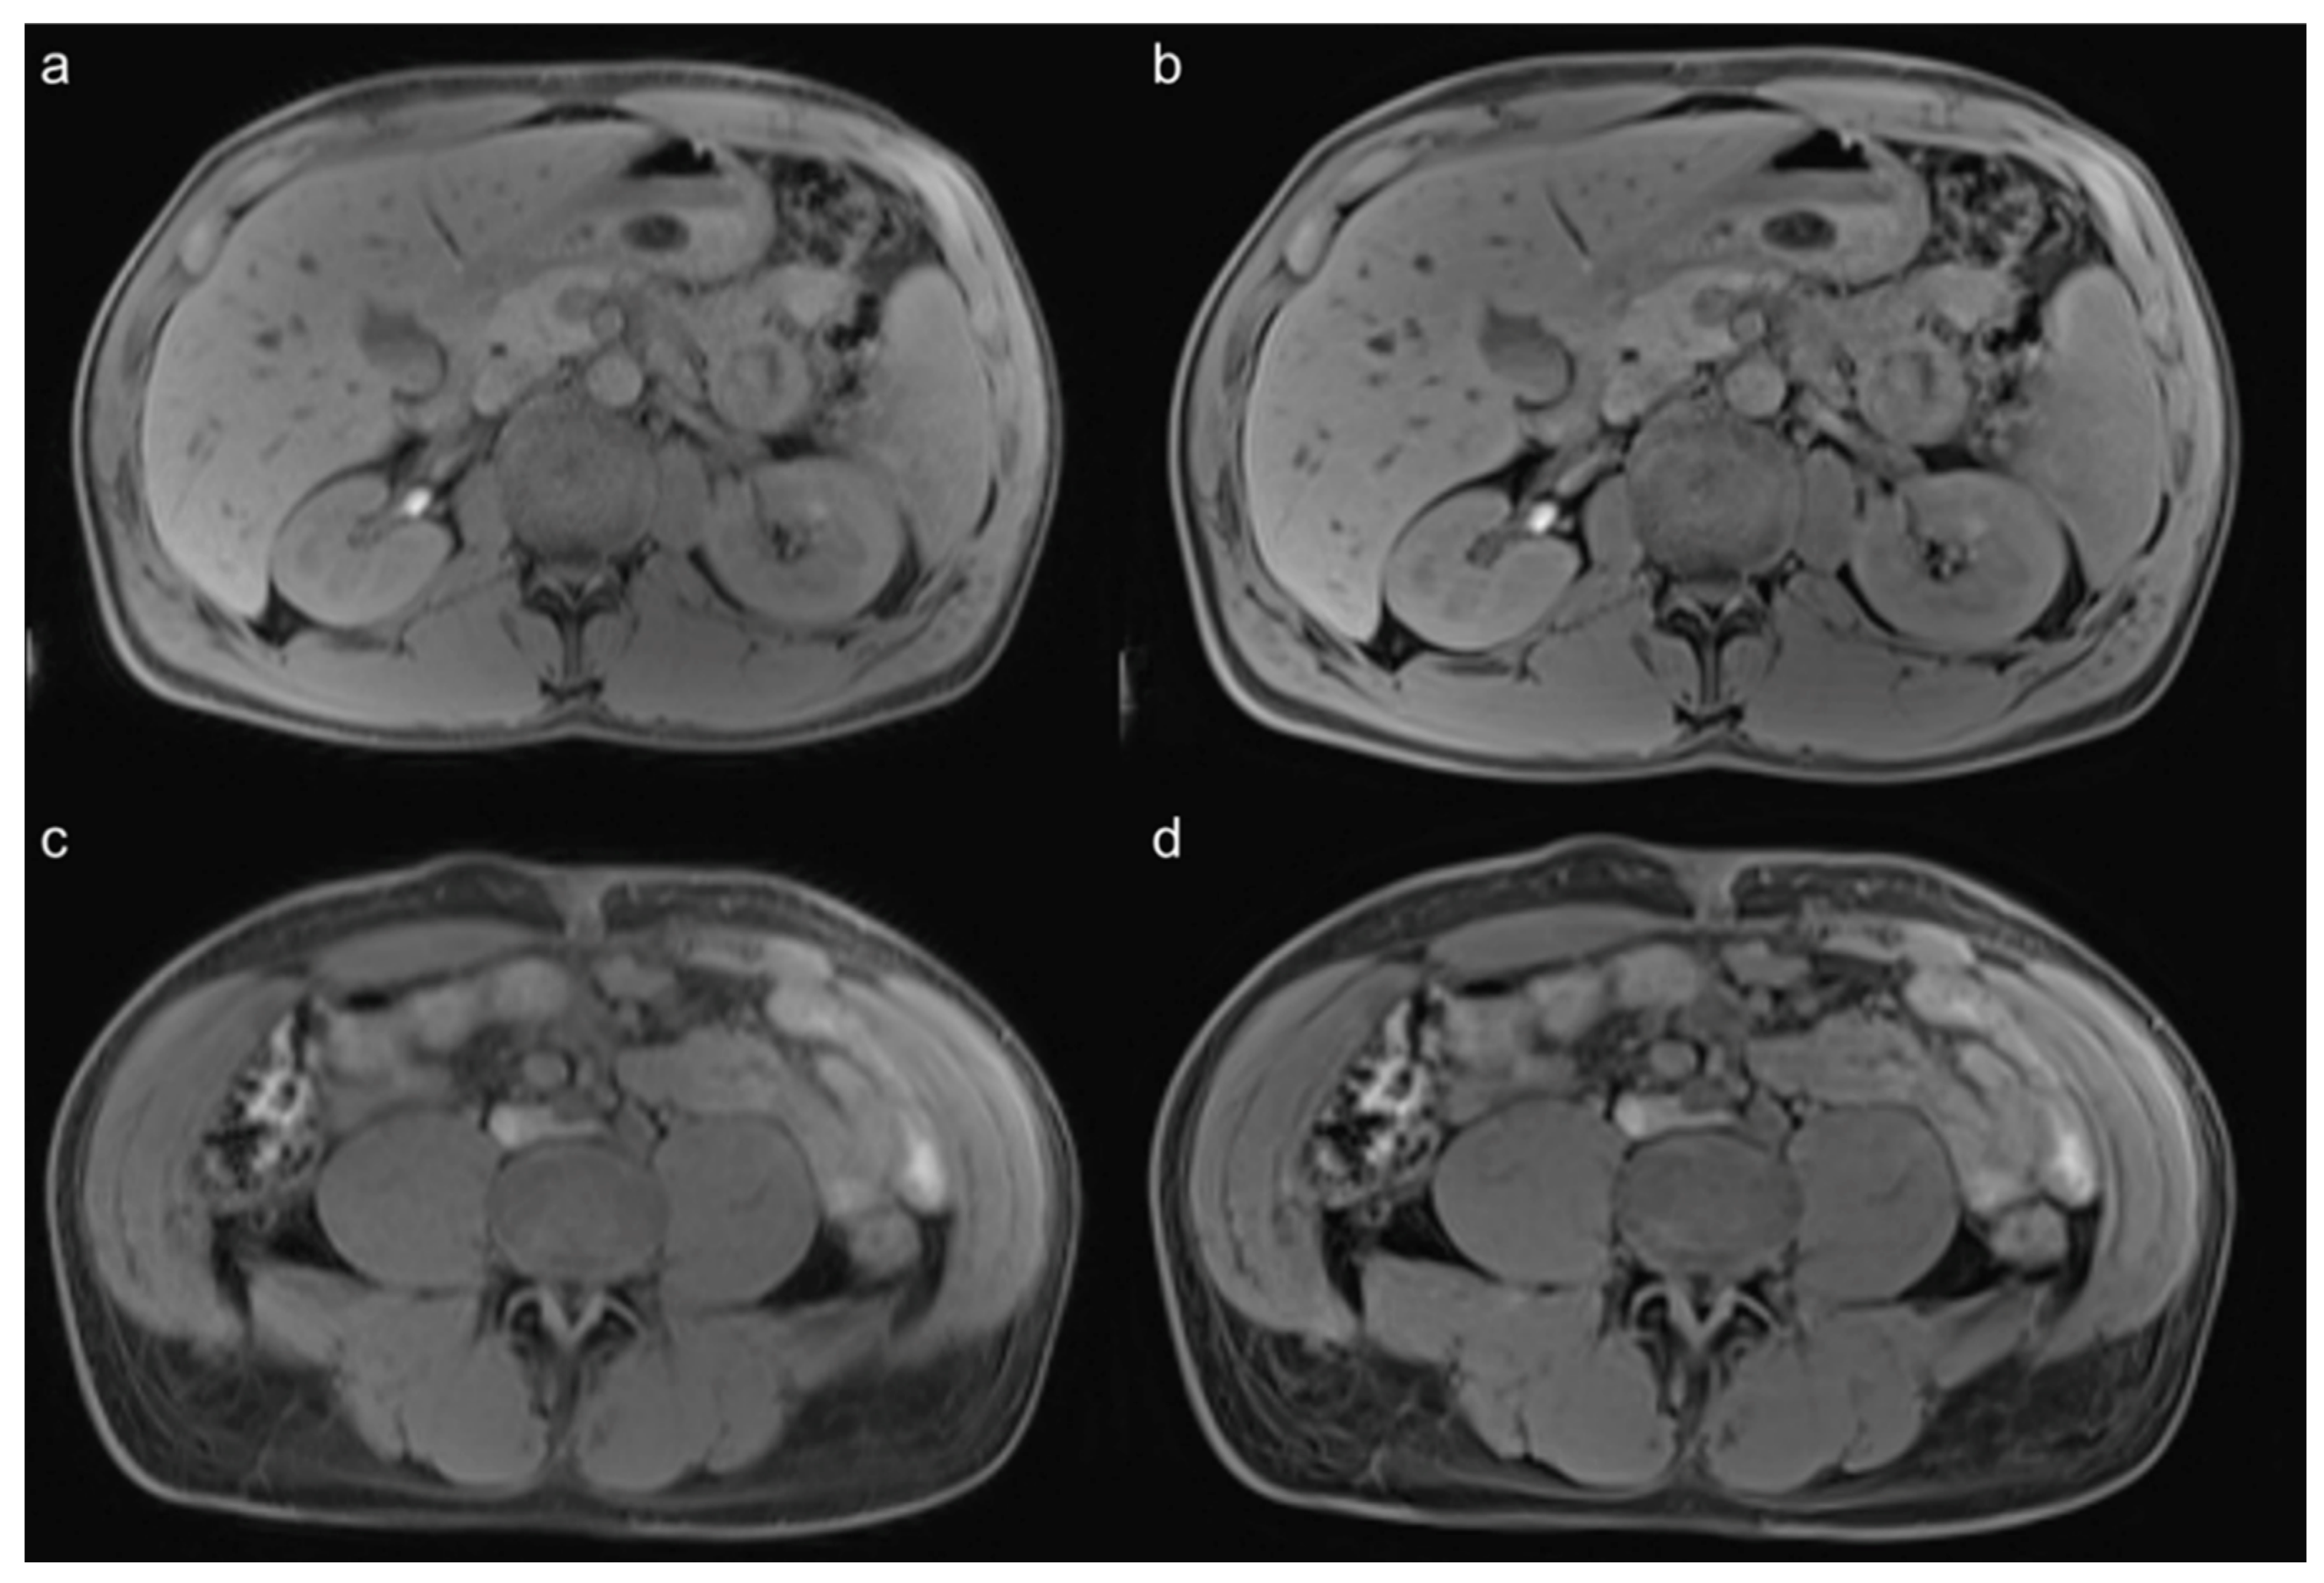

3.3. Qualitative Results of the Precontrast Images

3.4. Qualitative Results of the Postcontrast Images